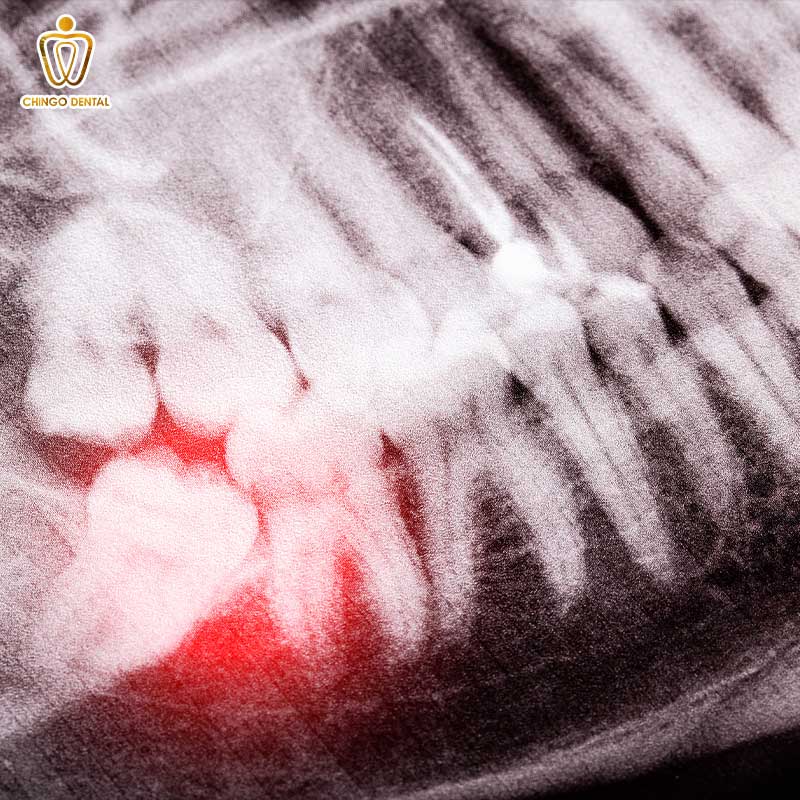

Do sự thu hẹp của xương hàm trong quá trình tiến hóa của loài người, răng số 8 hiếm khi mọc thẳng thuận lợi. Tình trạng răng số 8 mọc lệch là phổ biến nhất, khi răng đâm vào răng số 7 bên cạnh hoặc mọc chen chúc. Đặc biệt nguy hiểm là trường hợp răng số 8 mọc ngang 90 độ, đâm thẳng vào chân răng lân cận gây đau đớn dữ dội.

Ngoài ra, còn có tình trạng răng mọc ngầm hoàn toàn dưới xương hàm hoặc viêm lợi trùm răng số 8. Khi một phần nướu che phủ bề mặt răng tạo khe hở cho vi khuẩn và thức ăn tích tụ, gây nhiễm trùng kéo dài.

Đây là tình trạng phổ biến nhất và cũng là nguyên nhân chính gây ra những cơn đau răng số 8 dữ dội. Răng số 8 mọc lệch thường được chia thành nhiều cấp độ

Mọc lệch gần (đâm vào răng số 7): Đây là trường hợp “nguy tử” nhất. Trục răng nghiêng khoảng 45 độ, tì sát vào răng số 7. Điều này không chỉ gây đau mà còn tạo hố sâu khiến răng số 7 bị tiêu xương, sâu hỏng từ phía chân răng.

Khi răng không mọc đúng vị trí, nó tạo ra một “vùng trũng” vi khuẩn. Tình trạng nhổ răng số 8 có ảnh hưởng gì không thường được đặt ra, nhưng sự thật là việc KHÔNG nhổ mới thực sự ảnh hưởng. Nó dẫn đến tiêu xương chân răng số 7 – chiếc răng ăn nhai quan trọng nhất mà không có răng nào thay thế được.